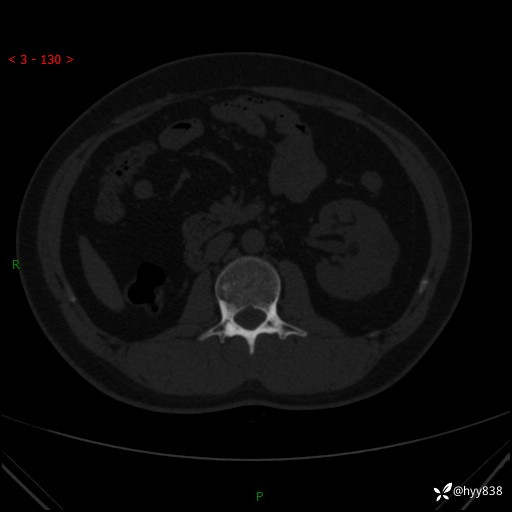

患者性别:男

患者年龄:28岁

简要病史:右肾肿瘤术后,常规复查

辅助检查:CT

临床诊断:右肾肿瘤术后

腹部CT+颅脑CT平扫